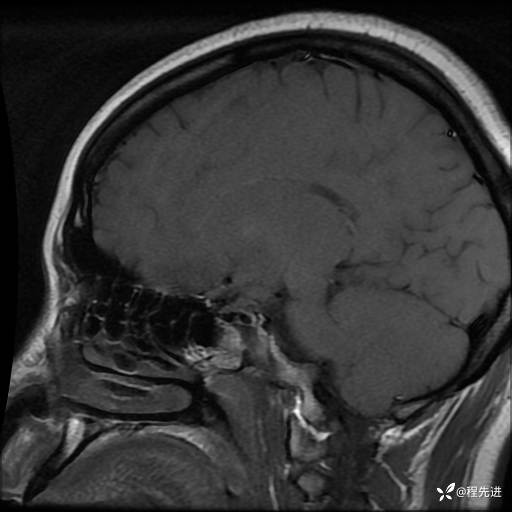

T1: